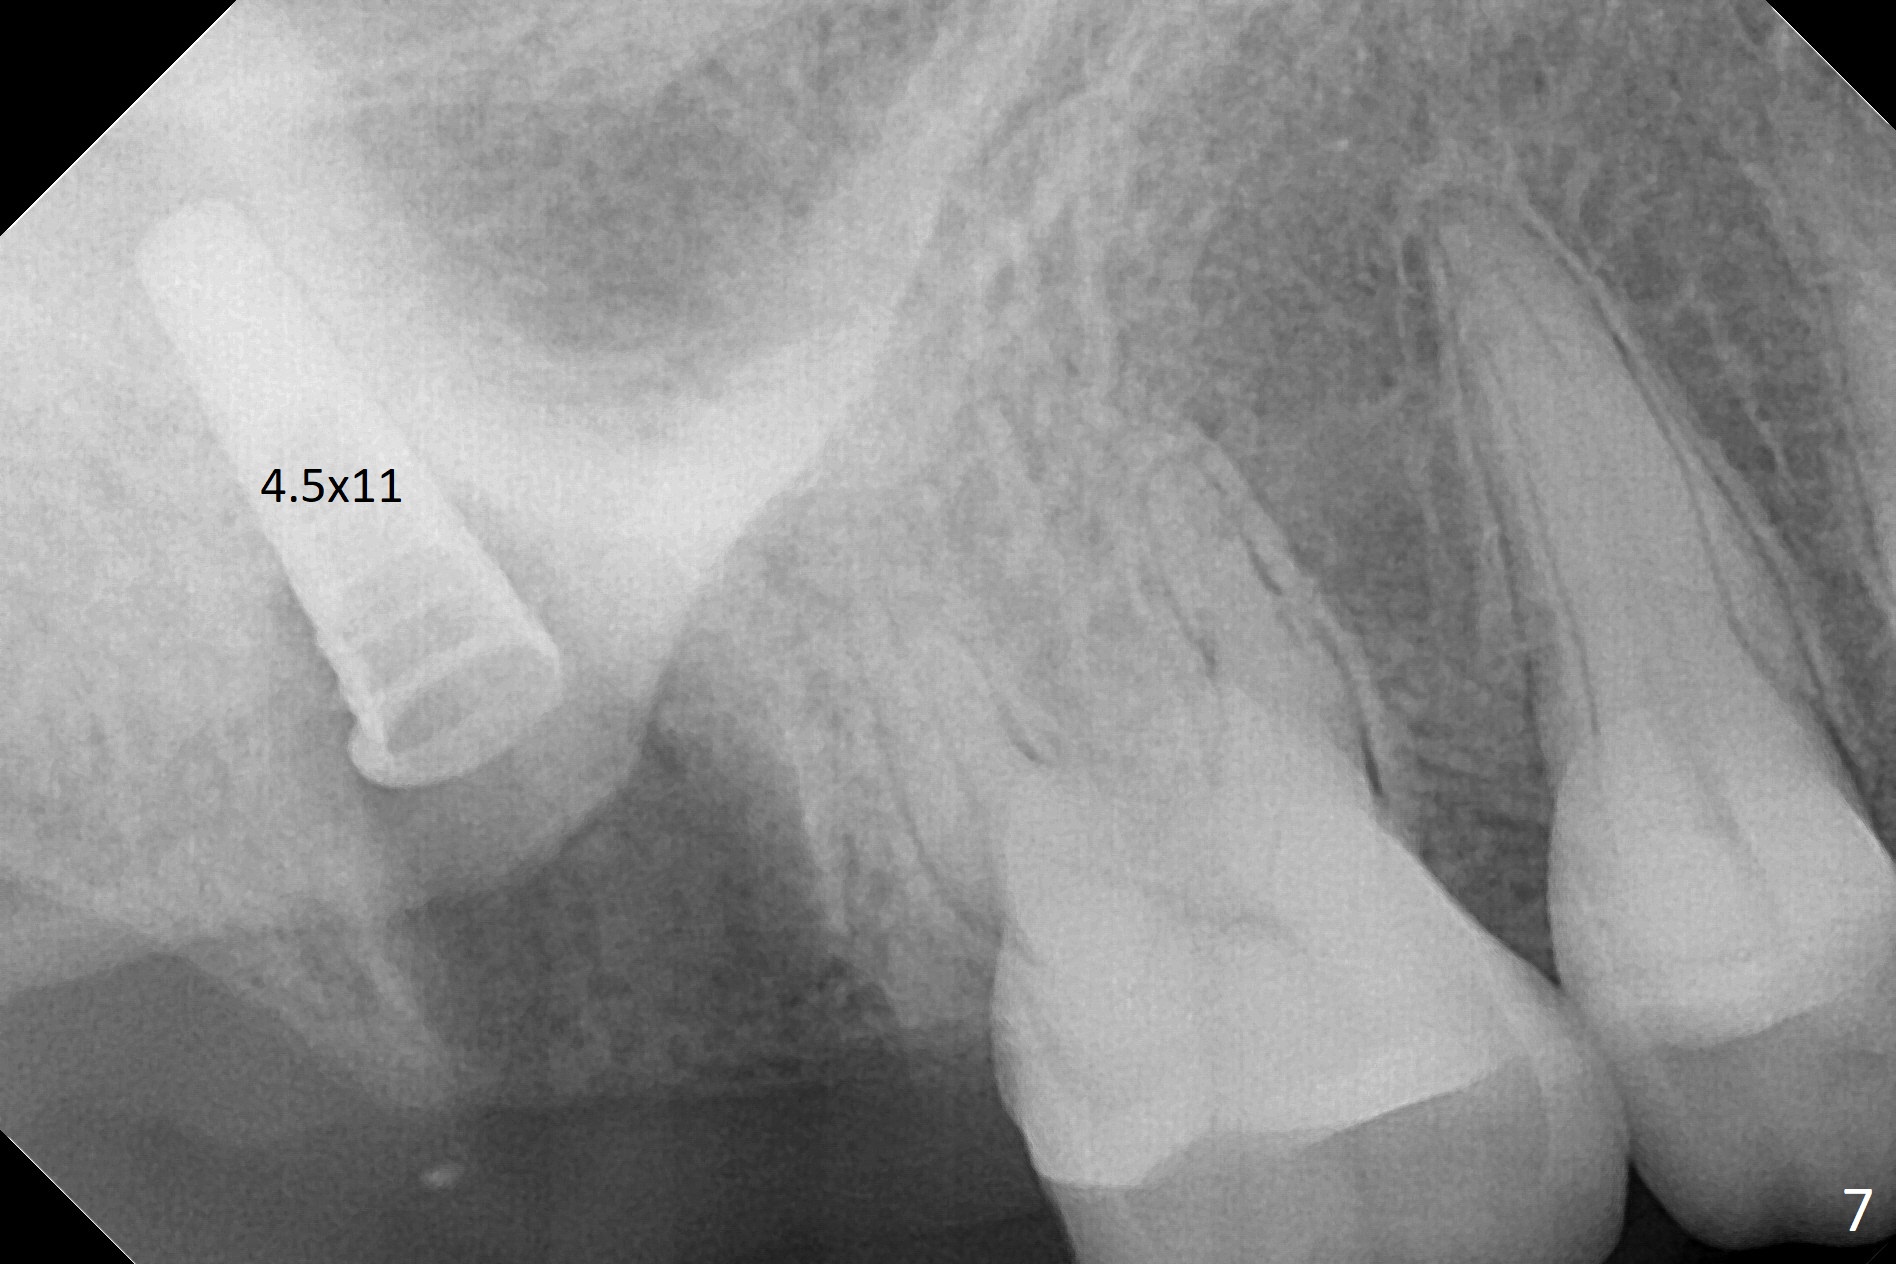

Fig.5 shows the mesial slope of the socket (M), which is more or less the center of the socket mesiodistally. If the osteotomy were set up in the red circle (Fig.6) in the mesial slope (Fig.8 green dashed line), the trajectory of 4.5x11 mm dummy implant (Fig.7) would be more ideal (Fig.8 red outline) with more native bone contact. Finally a longer IBS implant is placed (4.5x15 mm, Fig.9,10) to achieve primary stability (50 Ncm). When the provisional is removed for impression 3 months 10 days postop, the implant is found to have been placed distopalatally (Fig.13), which should have been avoided. It appears essential to use guide for a distal implant. It is agonizing to re-encounter the off-axial implant (Fig.14) and the distopalatal access hole (Fig.15) 1 year post cementation. It is also amazing that the abutment screw has not loosened. A fair-sized piece of bone graft has just been removed buccally (Fig.15,16). The patient complains of sensitivity 2 years 3 months post cementation, although there is no abnormality around the implant crown. Guided surgery is essential to avoid restoration complication. There is no thread exposure nearly 3 years post cementation; in fact the apical portion of the abutment is covered by the bone (Fig.17,18).